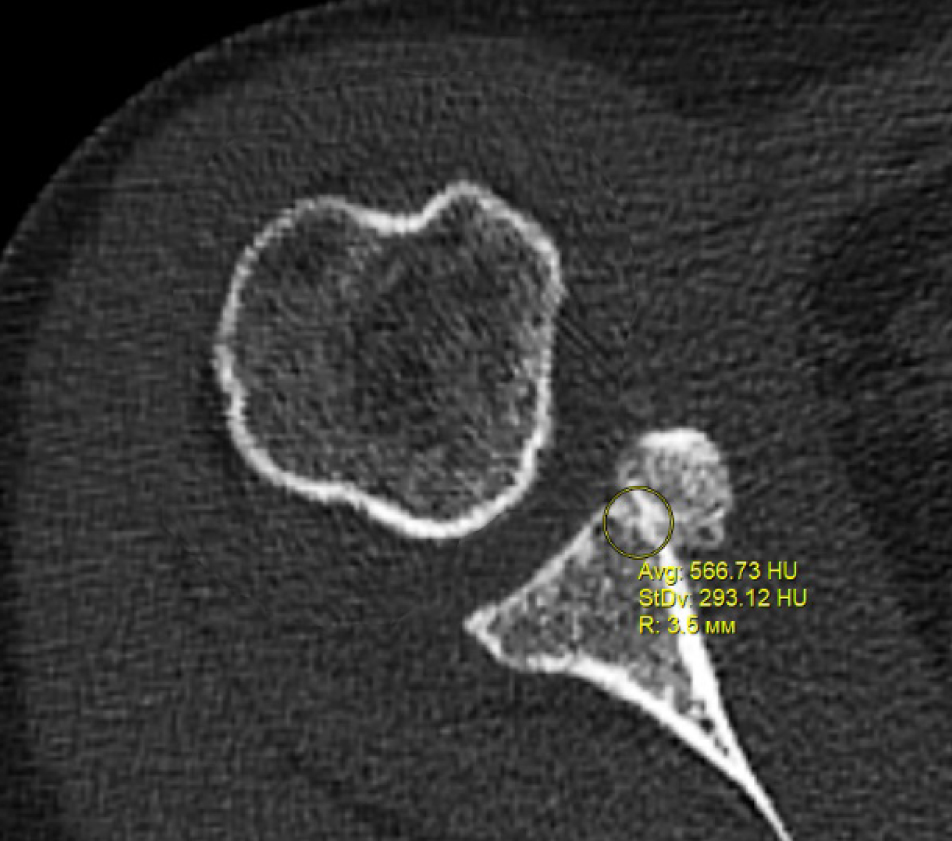

В программном обеспечении, на аксиальных КТ срезах оперированного плечевого сустава, выбирали инструмент «круг», который позволял посчитать среднюю плотность тканей внутри круга в единицах Хаунсфильда. Шкала единиц Хаунс-филда (HU) – шкалалинейного ослабления излучения по отношению к дистиллированной воде, рентгеновская плотность которой была принята за 0 HU (при стандартных давлении и температуре). Круг устанавливали таким образом, чтобы одна его половина была заполнена тканью гленоида, вторая половина тканью трансплантата (рис. 1–3). Оценивали плотность тканей над проксимальным винтом, между винтами, под дистальным винтом. Полученные данные анализировали с помощью пакета Microsoft Excel.

Рис. 3. Оценка плотности ткани над проксимальным винтом

Через 3 месяца после оперативного лечения по данным анализа КТ срезов были получены следующие результаты: плотность ткани над проксимальным винтом составили (424 ± 24,3) HU, между винтами (460 ± 23,4) HU, под дистальным винтом (587 ± 49,1) HU. Спустя 6 месяцев после операции плотность ткани над проксимальным винтом составили (320 ± 28,7) HU, между винтами (424 ± 36,2) HU, под дистальным винтом (623 ± 33,4) HU. Через 12 месяцев после операции показатели были следующие над проксимальным винтом (276 ± 22,1) HU, между винтами (387 ± 31,1) HU, под дистальным винтом (662 ± 43,2) HU (таблица).

Над проксимальным винтом | 424,0 ± 24,3 | 320,0 ± 28,7 | 276,0 ± 22,1 |